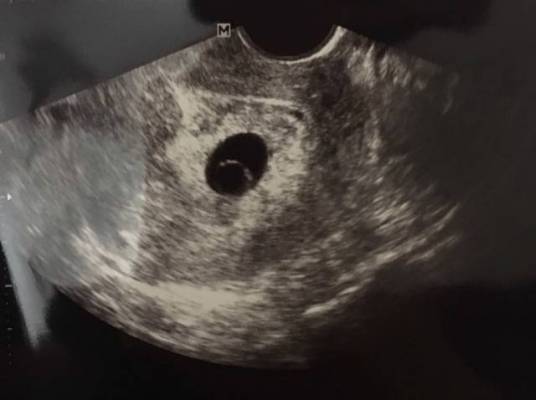

您的位置首页百科知识 卵黄囊 Simone 发布于 2025-10-07 21:31:04 866 阅读 卵黄囊的有关信息介绍如下:卵黄囊(yolk sac) 胚胎发生体褶后,原肠则明显地分成胚内的原肠和胚外的卵黄囊,内包有大量的卵黄,卵黄囊的壁由胚外内胚层和胚外中胚层形成。想要了解更多“卵黄囊”的信息,请点击:卵黄囊百科